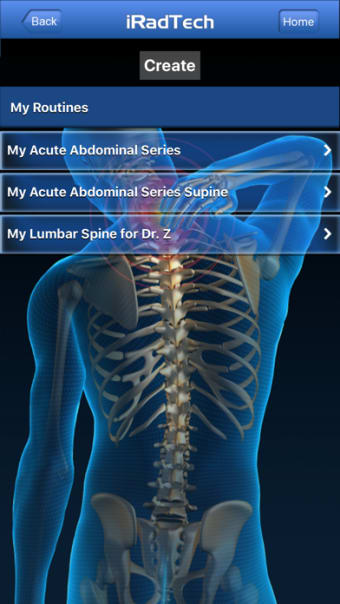

IRadTechهو برنامج إصدار كامل لأجهزة iPhone ، وهو جزء من فئة "الطب" أ>.

حول IRadTech لأجهزة iPhone